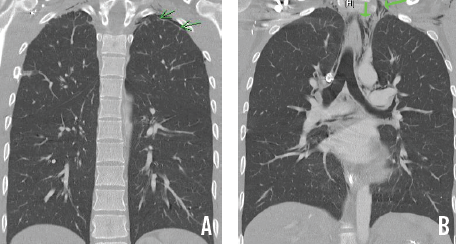

Deepa D. Kulkarni, MD; Gitanjli Arora, MD; Daniel A. DeUgarte, MD; Stephen B. Shew, MD

A 3,345-g boy was born at full term to a primigravid mother via an uncomplicated cesarean delivery for failure to progress.